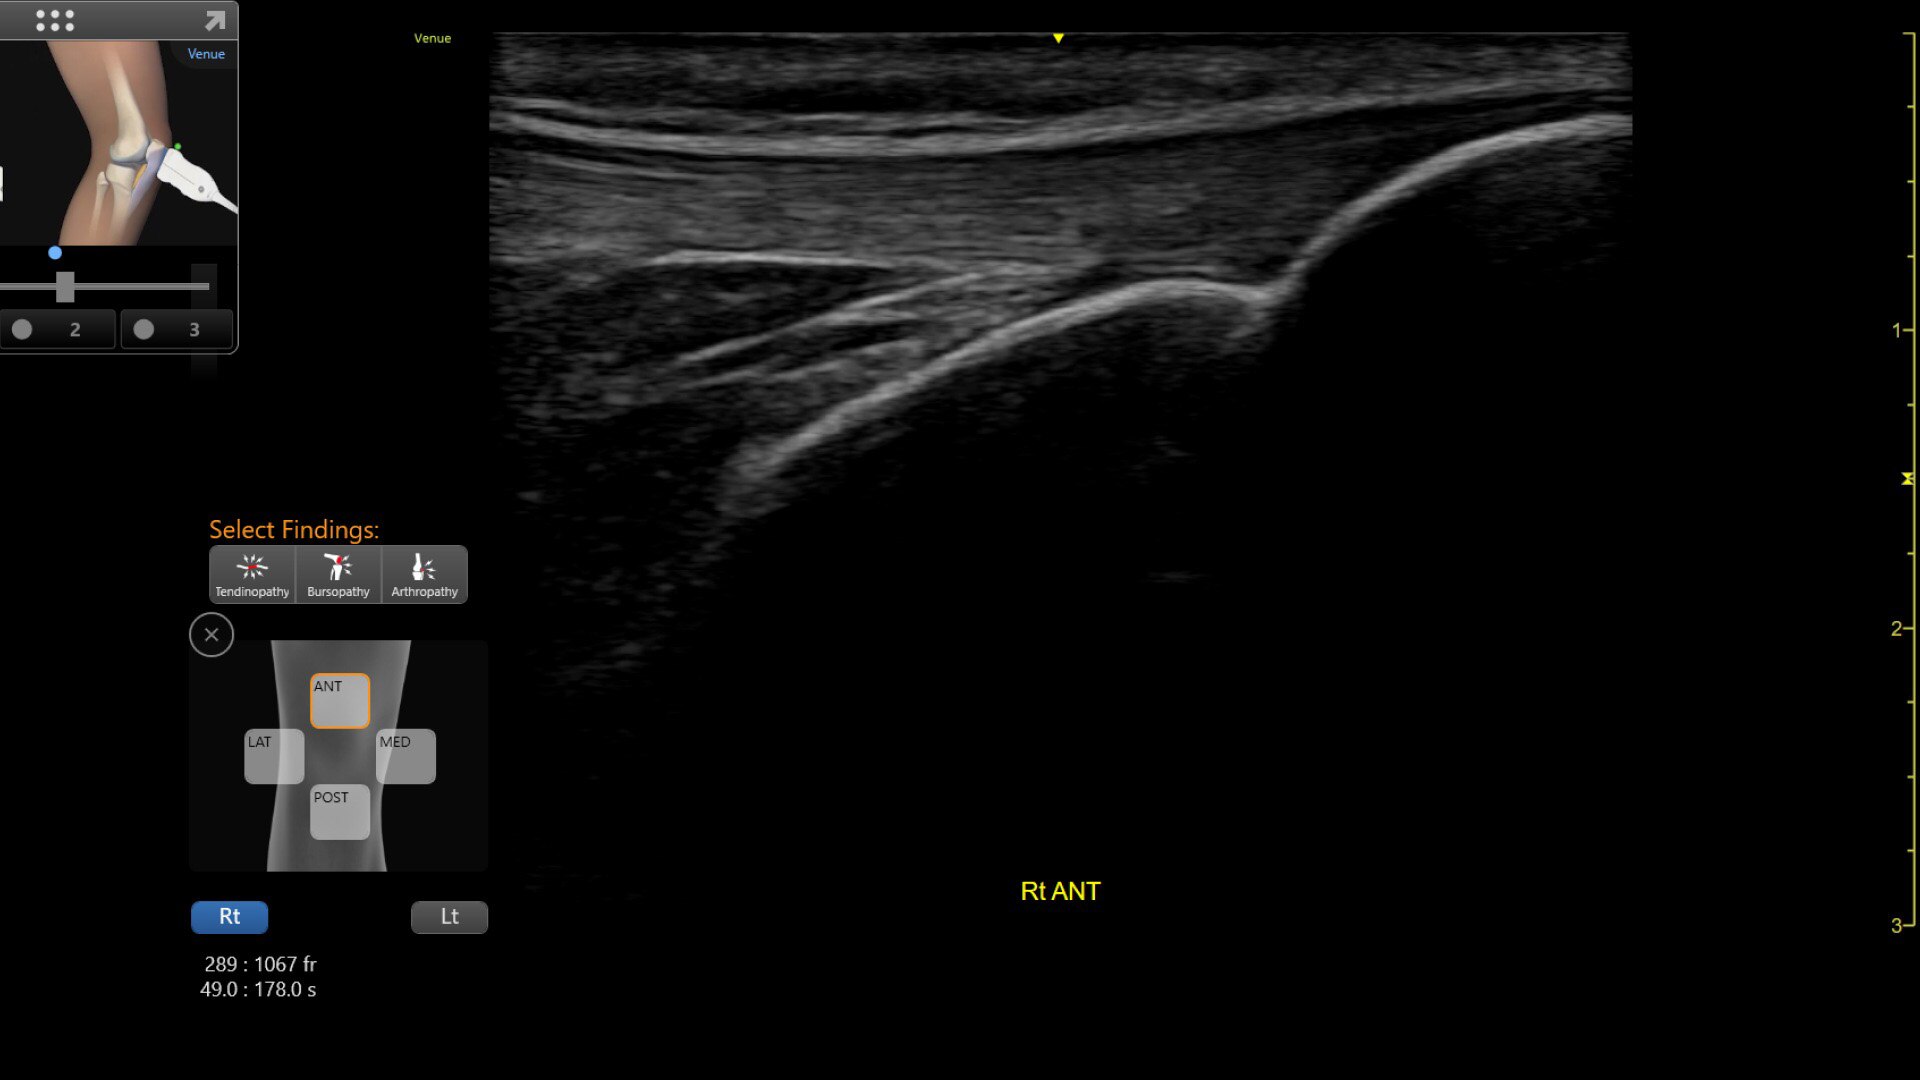

VENUE COACH MSK

Simplifying MSK scans

This easy-to-use exam documentation tool assists users through exams by providing reference images and anatomy markups. Multiple anatomical areas and helpful video tutorials help clinicians to acquire the scans they need.

• MSK Diagrams: Simplifies documentation and assists the clinician in follow up for patients. No need to manually type findings—you can simply assign a label from a pre-populated list that correlates with the images. Get a single view diagram with one click image storing, keep track of assessments and show trends in response to therapy.

• Reference Image: Reference image provides anatomy mark-ups to assist novice users in scanning the correct anatomy

• Bilateral mode: Helps you to view the opposite side of the same zone for comparison (available for Shoulder preset)

5-simplify-scan-desktop